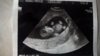

Gratulacje [emoji4] śliczne Maleństwo [emoji5]Hej ja dopiero wróciłam, nie dość ze godzinne opóźnienie miał to jeszcze tak dlugo w gabineciedzidziol zdrowy ma ok 4 cm

serce bije jak dzwon, nawet policzyl paluszki u rak

fikolki strzelal jak tatusia zobaczył

hehe. Za miesiąc wizyta, ale za dwa tyg jadę w ramach tej dzisiejszej wizyty bo dzis nie chcial sie pokazac a chcial zobaczyc jego twarzyczkę, zbadać przyziernosc karkowa itd

. Poniżej zdjęcie

Super!! Dzidzia jaka juz big!!!Hej ja dopiero wróciłam, nie dość ze godzinne opóźnienie miał to jeszcze tak dlugo w gabineciedzidziol zdrowy ma ok 4 cm